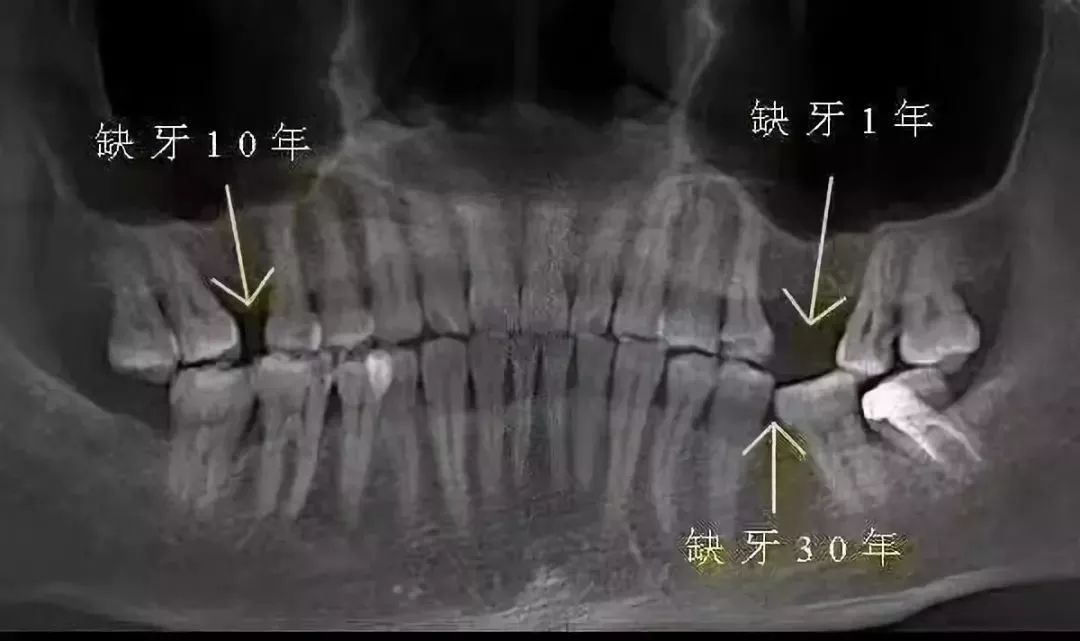

缺牙后不及时修复,牙槽骨会发生废用性萎缩。时间越长,萎缩越严重,等到想修复时,难度和费用都会增加,所以及时种上新牙很重要。